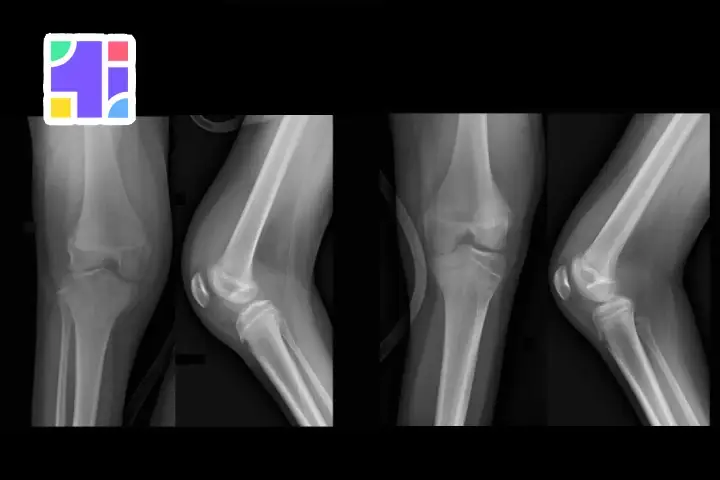

| رادیوگرافی (X-ray) | ساختار استخوان و وجود شکستگی یا آرتروز را نشان میدهد. | تشخیص آسیبهای استخوانی و آرتروز |